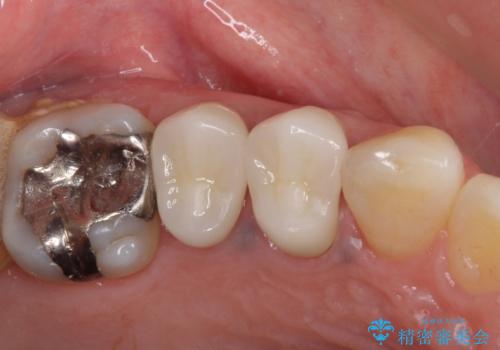

- 以前詰め物をした奥歯に物が頻繁に挟まるとのことで来院された患者様です。

充填物は形態が不正であり、歯肉付近にバリのように充填材料が飛び出していたため、歯肉が腫れやすい状態でした。